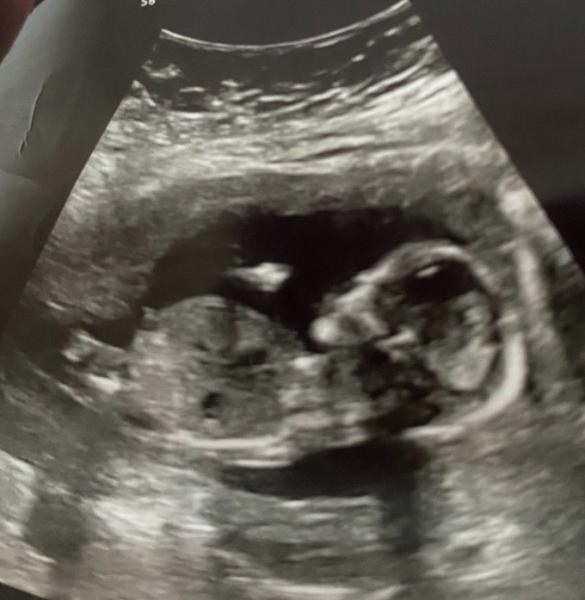

Halli Hallo meine Hübschen. Kennt sich Jemand mit der Nub Theorie aus und kann mir sagen was man auf dem Ultraschallbild sieht.

Ich habe mich mal belesen und denke, dass das Foto nicht geeignet ist, da nicht die Körpermitte getroffen wurde.

Oh schade . Ich kenne mich leider auch nicht aus. Ich weiß nur dass man ab der zwölften Schwangerschaftswoche den Nub Teil sehen kann. Danke für deine Antwort .